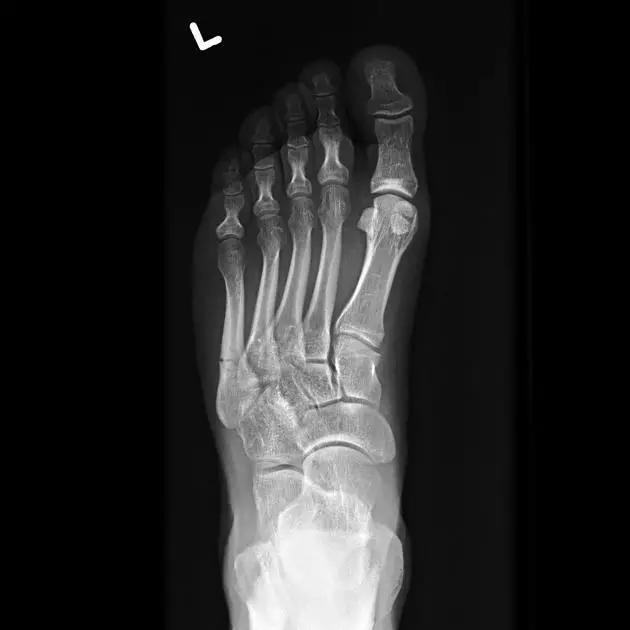

14.第五跖骨骨折

第五跖骨基底部骨折的不同类型:Stress 骨折;Jones 骨折:第五跖骨基底部以远 1 英寸内的骨折称为 Jones 骨折; Avulsion 骨折。

(来源:Radiopaedia)

Stress 骨折(来源:OrthoInfo-AAOS)

Jones 骨折正位片(来源:Radiopaedia)

Jones 骨折斜位片(来源:Radiopaedia)

第五跖骨骨折还有 dancer’s fracture。

dancer’s fracture 正位片(来源:footEducation)

dancer’s fracture 侧位片(来源:footEducation)